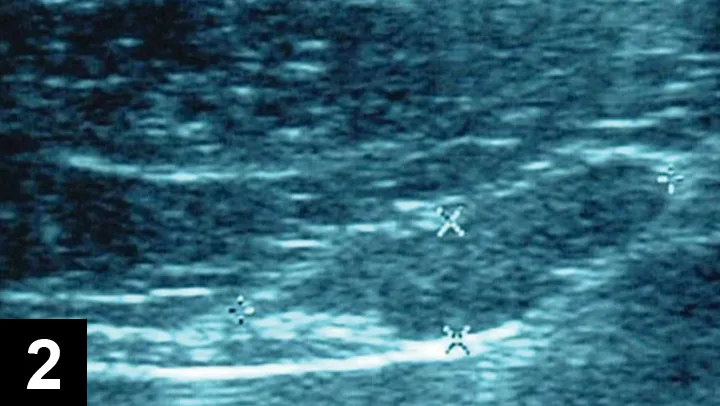

Figure 2

Abdominal ultrasound showing enlarged sublumbar lymph node.

Clinical staging involved 3-view thoracic radiography and abdominal ultrasonography. Evidence of intrathoracic abnormalities, including pulmonary metastasis, was absent on radiographs. Ultrasound abnormalities included an enlarged, heterogenous liver with diffuse multiple hypo­echoic foci, moderately enlarged spleen, and an irregular sublumbar lymph node measuring 3 cm in diameter (Figure 2). Ultrasound-guided, fine-needle aspirates of liver and spleen were collected. Cytology of liver aspirates was consistent with steroid hepatopathy (vacuolar degeneration); no abnormalities were noted on cytology of the splenic aspirates.